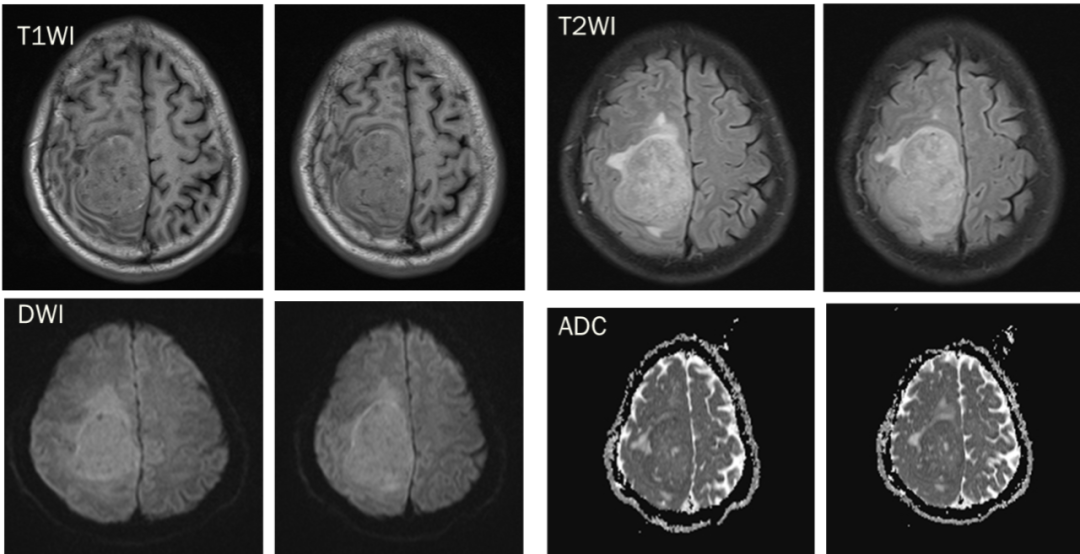

CASE 4

男,62 岁

右侧顶叶区混杂信号占位,T1、T2 内部条样低信号影,血管留空信号;增强可见明显强化,内部信号欠均匀,内见强化迂曲血管影。

诊断:右侧顶叶区血管外皮瘤